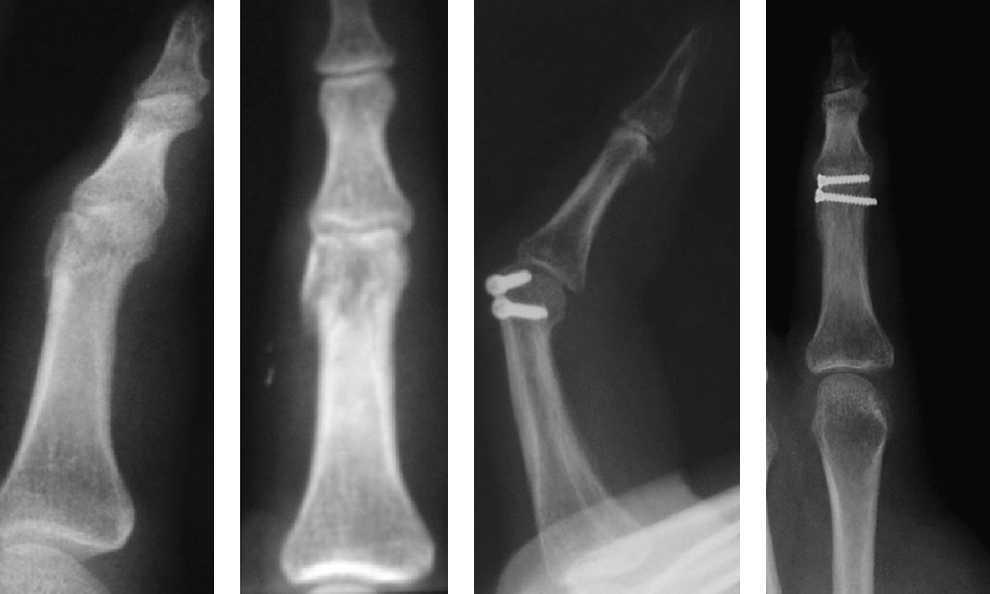

Las reducciones radiográficas de la fractura fueron aceptables desde el punto de vista anatómico en 78 (92,85%) casos. En 3 (3,57%) pacientes con fractura articular de la base de la falange conminuta hubo defecto de reducción de la fractura con una superficie articular corregida, en 2 pacientes (2,38%) no se consiguió corregir perfectamente la superficie articular debido a la gran conminución y a que los fragmentos óseos eran muy pequeños (referidos como malos resultados) y en un (1,19%) paciente con fractura de la falange proximal del cuarto dedo quedó una ligera diástasis del foco de fractura, tras tener un traumatismo en el dedo la fractura se desplazó y se lo intervino para colocarle una placa y tornillos (referido como mal resultado [figura 5).

Figura 5. Fractura oblicua larga de la falange proximal del dedo anular de la mano derecha. Fracaso de osteosíntesis percutánea. Nueva osteosíntesis con placa y tornillos.

Las complicaciones imputables a la técnica solamente se han observado en 3 pacientes, en uno de ellos la fractura no quedó suficientemente estable y al recibir el paciente un traumatismo sobre el dedo se desplazó y movió los tornillos, por lo que precisó una nueva intervención mediante osteosíntesis con placa y tornillos, con buenos resultados posteriores (figura 5). En 2 pacientes no se consiguió la reducción anatómica articular adecuada, aunque probablemente si se hubiera intentado la reducción abierta el resultado habría sido igual o peor debido al tamaño reducido y a la gran conminución de los fragmentos óseos.